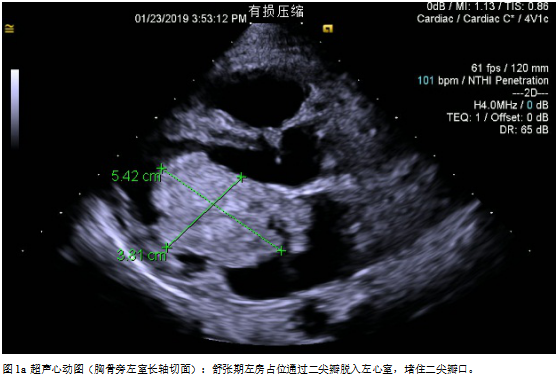

诊断:左房占位主要根据间断胸闷憋喘伴咳嗽等临床症状结合影像学主要是超声心动图评估作出诊断;根据超声心动图检查,可见左房占位蒂附着于房间隔左房面与卵圆窝相应的位置,单发,通过形态及活动度,考虑为单纯粘液瘤。

手术:目前左房粘液瘤患者手术指征粘液瘤可阻塞瓣膜开口导致心力衰竭或心跳骤停,瘤栓脱落导致脑检塞等也可以引起死亡。因此,一且确诊,立即争取手术治疗。一般心脏患者如有长期发热、心力衰竭、贫血、血沉增快等现象,须延缓手术。但对心脏粘液瘤患者需具体分析,否则可能丧失手术机会。如有高热、血沉快,全身症状为主要表现,并且考虑是由粘液瘤引起,应立即手术,摘除肿瘤能使体温下降、心率变慢、血沉恢复正常、心衰得到控制。如果感染性心内膜炎引起的高热、心力衰過,不宜急于手术,应该控制高热、心衰后手术,以免发生严重的并发症[1-2]。该患者左房占位病变巨大,且血流动力学不稳定,肿物随左心室舒张通过二尖瓣从左房脱入左室,左心室收缩又返流回左房,因粘液瘤部分阻塞二尖瓣口,随体位变化有间歇性昏厥的患者,我们选择严格限制卧床体息,应用静脉滴注多巴胺强心维持血压,同时给予利尿药减轻肺水肿,准备急症手术。